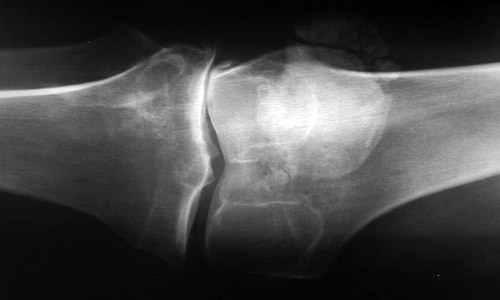

The knee shown here demonstrates joint space narrowing along with joint subluxation in a patient with marked osteoarthritis. The knee, a prime weight-bearing joint, is a common area of involvement with degenerative osteoarthritis